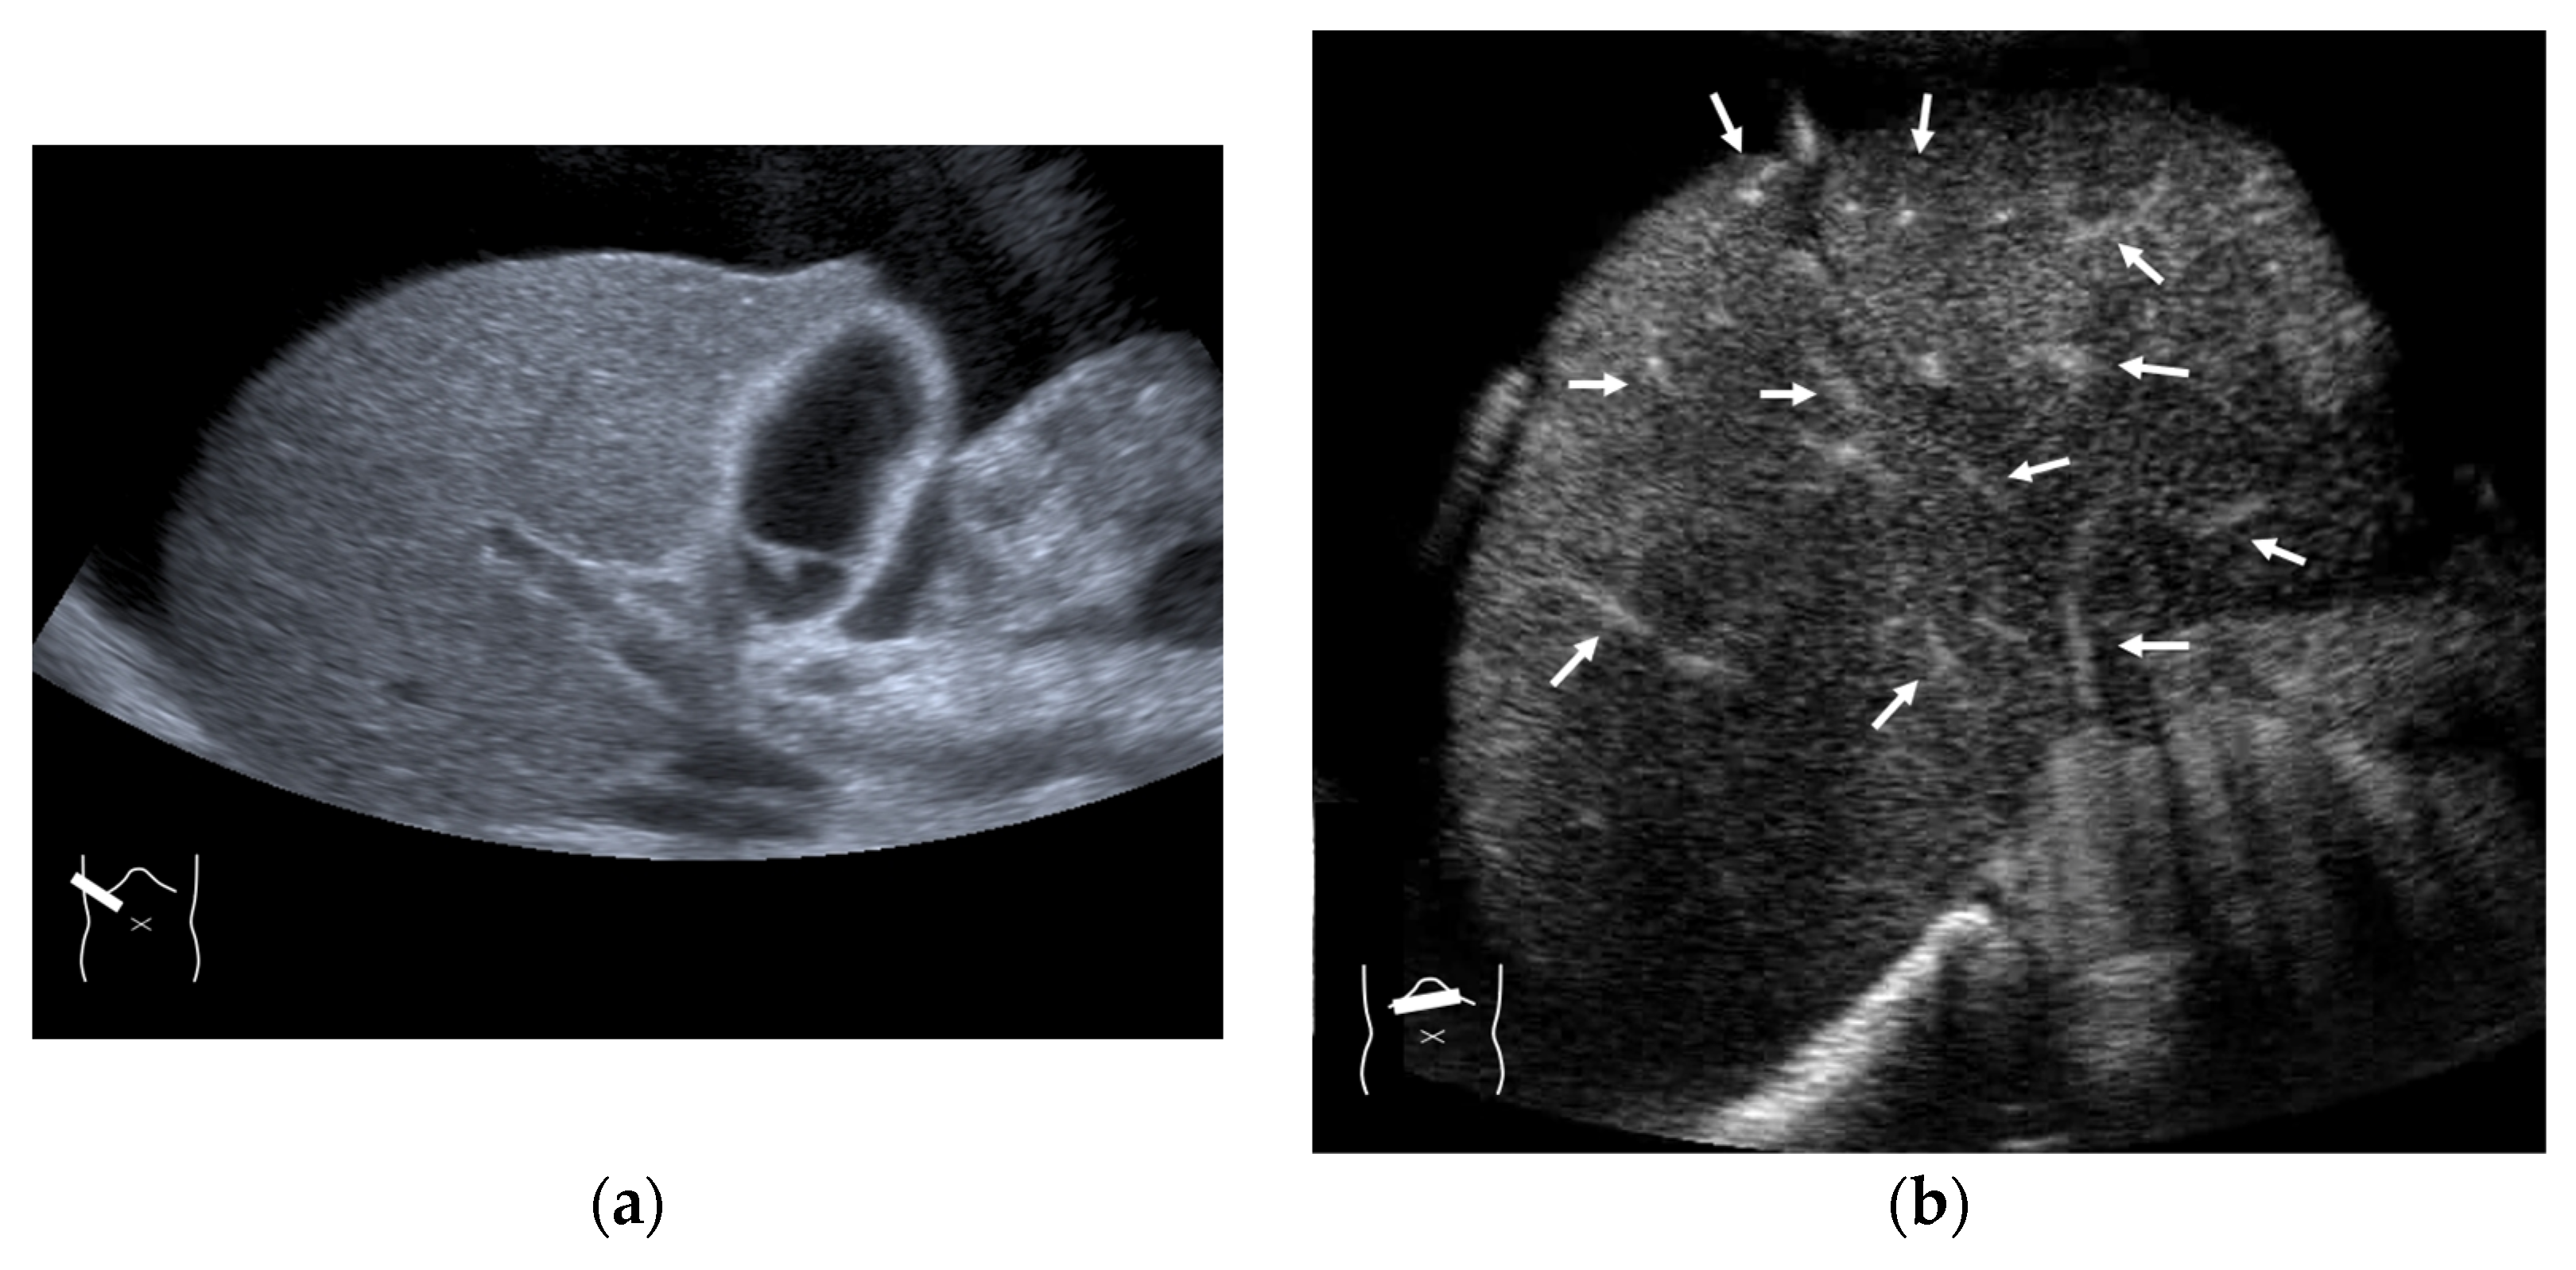

4.3. Budd–Chiari Syndrome

- Grus, T.; Lambert, L.; Grusová, G.; Banerjee, R.; Burgetová, A. Budd-Chiari Syndrome. Prague Med. Rep. 2017, 118, 69–80. [Google Scholar] [CrossRef] [PubMed]

- Yusa, T.; Okabe, H.; Yamashita, Y.I.; Nitta, H.; Nakao, Y.; Itoyama, R.; Yamao, T.; Higashi, T.; Yamamura, K.; Imai, K.; et al. A case of inferior right hepatic vein-right hepatic vein bypass with interrupted inferior vena cava compressed by focal nodular hyperplasia in caudate lobe. Int. Cancer Conf. J. 2020, 10, 11–14. [Google Scholar] [CrossRef] [PubMed]

- Ning, J.; Aini, Y.; Jiang, T.; Shao, Y.; Aji, T.; Wen, H. Intrahepatic venous collateral circulation and reverse blood flow after main hepatic vein obstruction: A case report with literature review. Ann. Transplant. 2023, 28, e941521. [Google Scholar] [CrossRef]